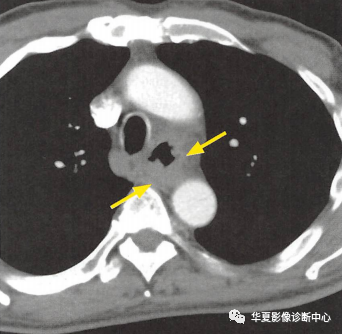

(上圖:增強CT食管壁不規則增厚)